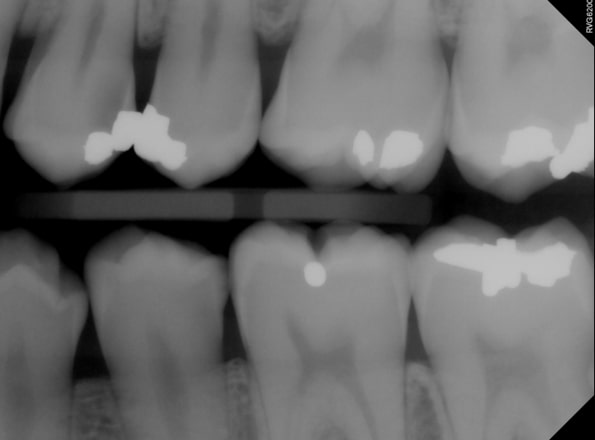

Typically, a post-op bitewing is taken to confirm the proper adaptation of restorative material to tooth structure, mainly when deep margin elevation is used to elevate a margin for indirect restorations. Deep margin elevation can be utilized near the bone with negligible effects on the biologic width when performed in a limited area.

In some cases, the matrix band may need to be adapted to accommodate the prep’s subgingival aspect. A #2 Tofflemire band or a modified #1 Tofflemire band can extend the matrix to ensure an adequate seal of the margin elevation material to the tooth.

Deep margin elevation has been shown to provide predictable long-term survival rates up to a decade after its performance. It’s yet another tool in our toolbox for managing subgingival preparations.